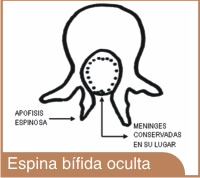

ESPINA BÍFIDA OCULTA:

La forma más leve produce una pequeña separación o un pequeño hueco en uno o más de los huesos (vértebras) de la columna vertebral. Debido a que los nervios raquídeos generalmente no están afectados, la mayoría de los niños con esta forma de espina bífida no tienen ningún signo ni síntoma, y no experimentan ningún problema neurológico.

La mayoría de las personas que tienen esta forma de Espina Bífida, ni siquiera lo saben y se dan cuenta cuando les hacen alguna radiografía de la espalda o por alguna otra razón.